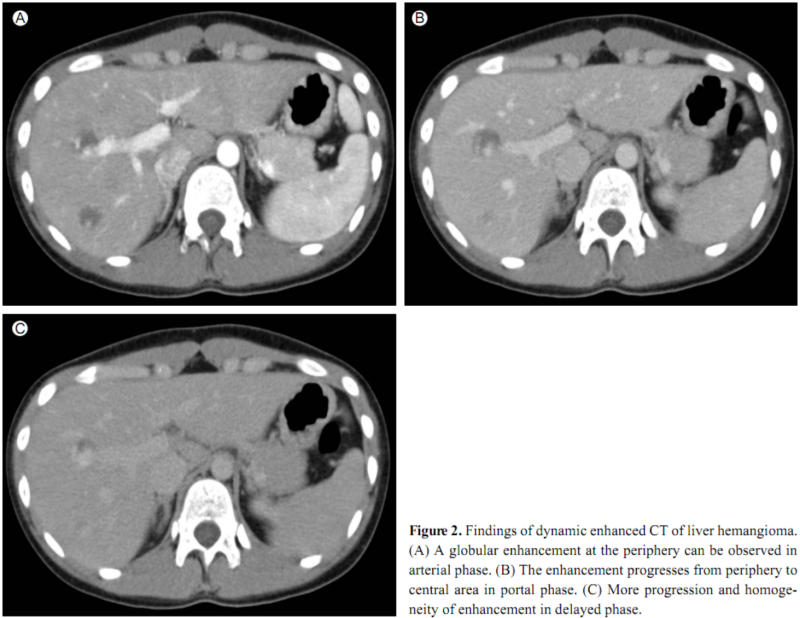

초음파 시 고에코 간내결절은 대부분 간혈관종초음파 시 고에코 간내결절은 대부분 간혈관종초음파에서 고에코 형태로 확인되는 간내결절은 대부분 간혈관종으로 간주됩니다.간혈관종은 간에 있는 모세혈관이 뭉쳐서 덩어리를 만든 형태의 종괴로 일종의 혈관 기형이라고도 할 수 있습니다.대부분 양성으로 암을 걱정할 필요가 없는 상태라고 할 수 있고 간결절에서 발견되는 대부분은 간혈관종인 경우가 많습니다.즉, 간혈관종으로 알려진 간결절이라면 별도 정밀검사 또는 조직검사 등을 하지는 않지만 크기 등의 변화가 있는지 등을 주기적으로 확인해 양성결절임을 꾸준히 확인해야 합니다.CT 검사를 실시해야 하는 간헐절(간혈관종)CT 검사를 실시해야 하는 간헐절(간혈관종)간결 때는 대부분 양성, 크기에 관계 없이 무증상의 경우가 많아 크게 걱정하지 않아도 좋다고 말씀 드렸습니다.그러나 문제는 증상이 나타나거나 크기에 변화가 발생한 경우, 그리고 초음파 검사 직후 그렇지만 바로 CT검사를 하고 볼 필요가 있는 경우가 있지만 간헐 마디의 모습이 초음파상 혈관종인지 악성 종양인지 명확히 확인하기 어려울 때입니다.복부 CT검사를 이용하면 정밀 검사가 가능하며 간헐 마디가 양성인지 악성인지를 확인할 수 있습니다.또, 간결 마디의 추적 관찰 중에 결절의 크기가 커지는 등의 변화가 나타나면 악성 여부 정밀 검사가 다시 필요하므로 CT검사가 필요합니다.만성 감염, 간 경변증, 간 암의 환자는 줄기 혈관 종양이나 종양의 악성 유무 등의 감별이 더 어려운 경우가 있으므로 CT검사로 정확한 진단을 받는 것이 좋습니다.또 간내 결절이 줄기 혈관종의 경우는 무증상인데 간이 있는 부위인 우상 복부에 통증이 있거나 부은 느낌인 팽만감 등이 있으면, 간결절 악성 종양의 유무를 확인하는 것이 아니라 주변의 다른 장기의 질환의 영향일 가능성이 있고 다른 질환에 대한 검사가 필요하게 되는 일이 있습니다.우리베스트내과 초음파와 CT검사를 이용한 간검사우리베스트내과 초음파와 CT검사를 이용한 간검사저희 베스트 내과에서 이용하는 초음파와 CT 기기를 소개해 드리겠습니다.우리베스트내과 초음파 기기는 프리미엄 초음파로 스캔 시간을 줄이고 미세 병변 측정이 가능해 간경변증 및 간종양(간암) 진단에 정확도를 높일 수 있습니다.저희 베스트내과 CT는 64채널 128슬라이스로 병변 위치를 정확히 파악할 수 있으며 고해상도 결과를 보여 미세 병변 진단이 가능합니다.진단의 정확도는 신속한 질환 확인을 통한 신속한 치료가 가능하다는 것을 의미합니다.본 베스트내과에서 간 건강관리 및 초음파와 CT검사 등 영상기기로 정밀검사를 받으실 수 있습니다.간검사 및 건강검진, 초음파, CT검사 우리베스트내과에서 검사를 받으려면 예약을 먼저 진행해야 합니다.예약방법(문의,상담포함)저희 베스트내과는 평일 오후 7시까지 진료하고 있습니다.저희 베스트내과는 평일 오후 7시까지 진료하고 있습니다.